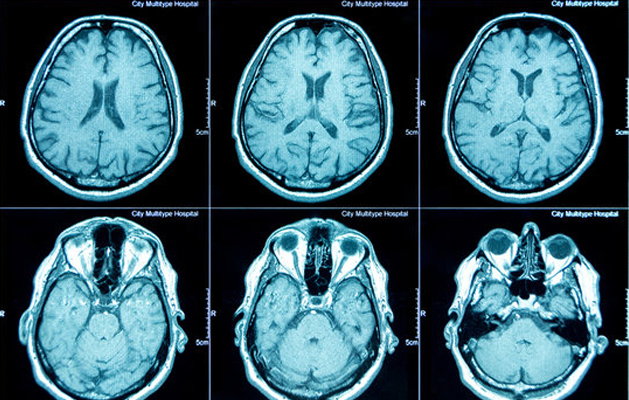

Best Clinical CT SCAN 24 Hours in Chennai

Computed Tomography (CT) scan is a powerful X-ray procedure that produces detailed pictures, or slices, of the body. It is also called computerized tomography and computed axial tomography (CAT). A CT scan shows detailed images of any part of the body, including the bones, muscles, fat, and organs. CT scans are more detailed than conventional X-rays. A special machine linked to a computer makes the CT images. The images can then be examined on a computer screen or printed. CT scans are painless and noninvasive. No anesthesia is needed. The radiation exposure from a CT scan is low compared with other diagnostic tests such as conventional X-rays. During a CT scan, you lie on a narrow table that slides through the center of the machine. You may be asked to hold your breath for short periods of time to avoid blurring the images. The test takes about 30 minutes. The information from a CT scan can be used to diagnose problems such as infections, tumors, bleeding in the brain, or injuries to the spine or organs. It can also help guide procedures such as surgery or biopsies (removal of tissue samples).